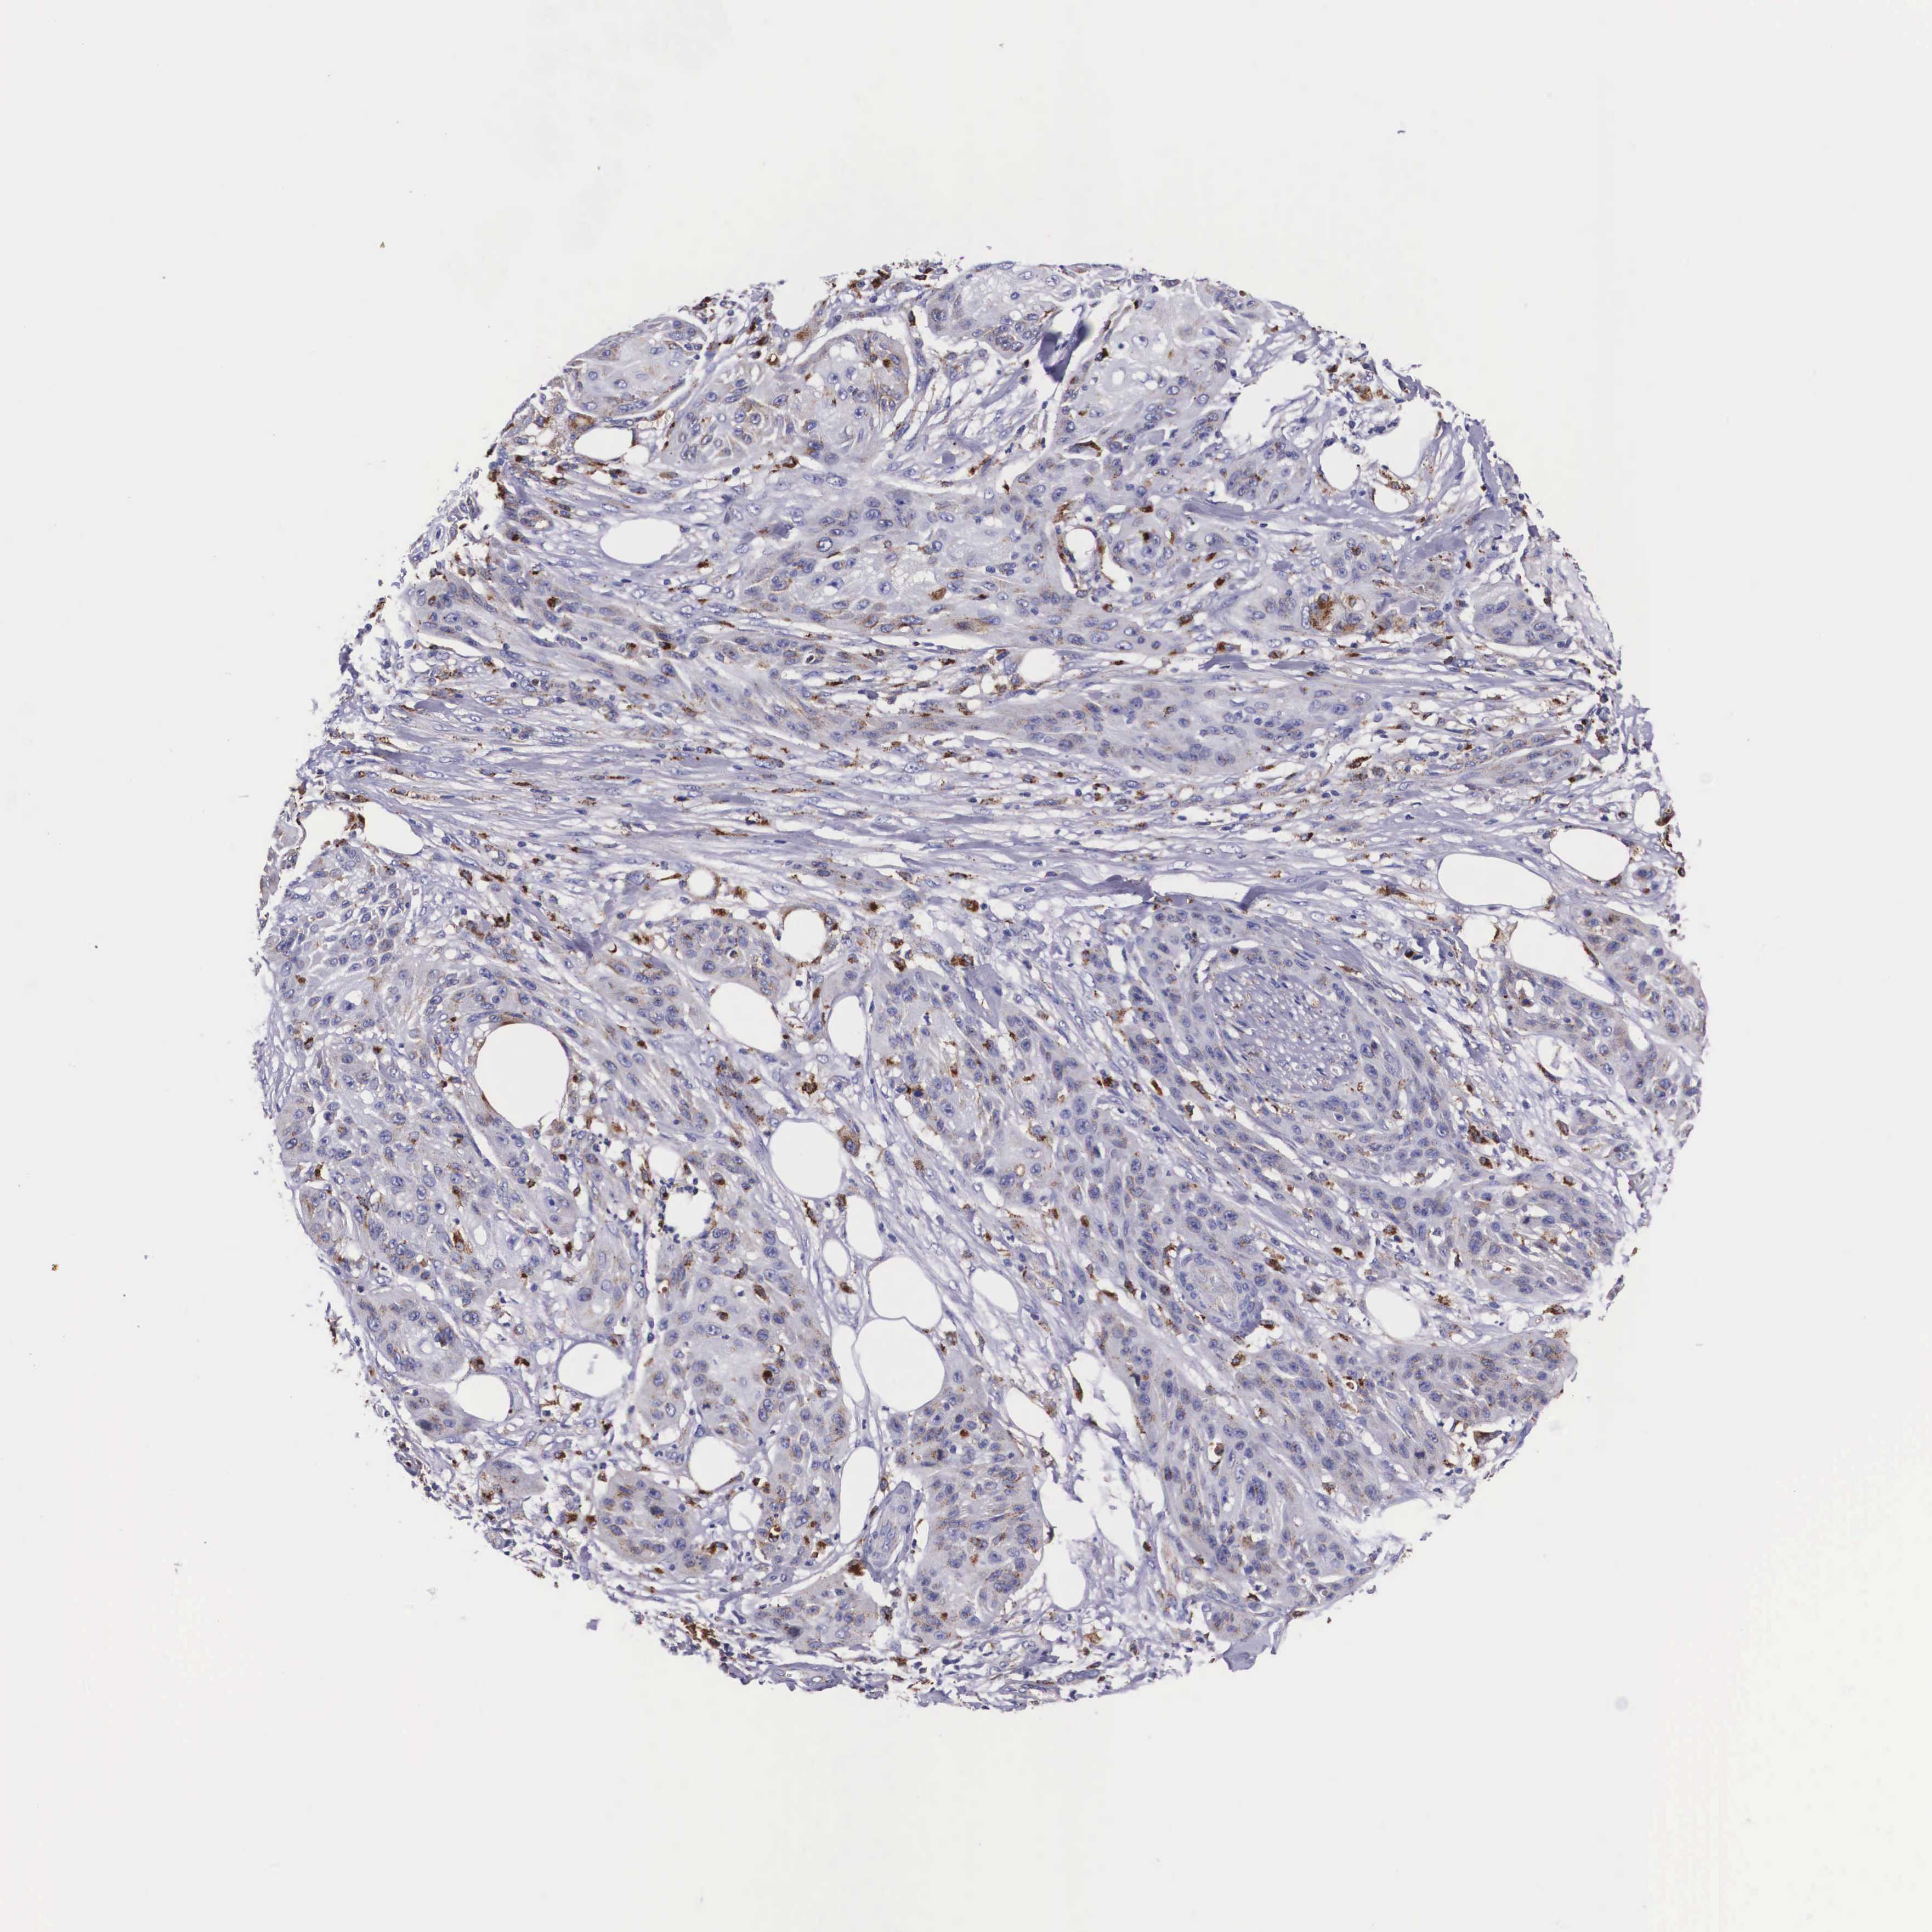

SKIN CANCER - Protein expressioni

A mouse-over function shows sample information and annotation data. Click on an image to view it in a full screen mode. Samples can be filtered based on level of antibody staining by selecting one or several of the following categories: high, medium, low and not detected. The assay and annotation is described here.

Antibody staining in the annotated cell types in the current human tissue is reported as not detected, low, medium, or high, based on conventional immunohistochemistry profiling in selected tissues. This score is based on the combination of the staining intensity and fraction of stained cells.

Each image is clickable and will lead to virtual microscopy that enables deeper exploration of all samples and also displays staining intensity scores, fraction scores and subcellular localization as well as patient and tissue information for each sample.

Antibody HPA000649

Staining

High

Medium

Low

Not detected

Intensity

Strong

Moderate

Weak

Negative

Quantity

>75%

75%-25%

<25%

None

Location

Nuclear

Cytoplasmic/membranous

Cytoplasmic/membranous,nuclear

Squamous cell carcinoma, NOS

Basal cell carcinoma